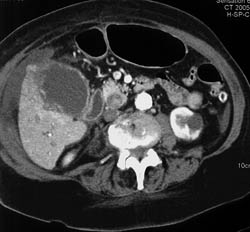

Acute Cholecystitis